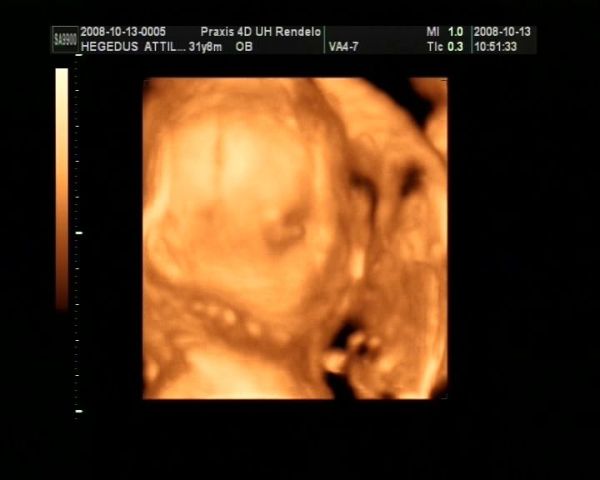

Tegnap voltunk 4d-s uh-on :) Hatalmas élmény volt. Viszont lesz egy komoly beszélgetésem a kisfiammal :) El kell magyaráznom neki, hogy a lányokra még nézni is csak szépen szabad, homlokon rugdosni őket pedig abszolút tilos. Még nézni is fájt, hogy miket művelt Eszterrel... Konkrétan az arcába ült, vagy a combját nyomta a nyakához, egyszer meg sarokkal homlokon rúgta. Mekkora harcok mehetnek bent... Eszterkém pofijáról nem is készült sok jó kép, mindegyiken belelóg Ádám feneke. Egyébként csodaszép két kölök, és makkegészségesek. Most épp fejjel lefelé voltak mindketten, de ahogy elnéztem őket ez egyelőre még kb 10 percenként változik :) És akkor a képek:

Ádámbátyám:

Kép

És Eszter: